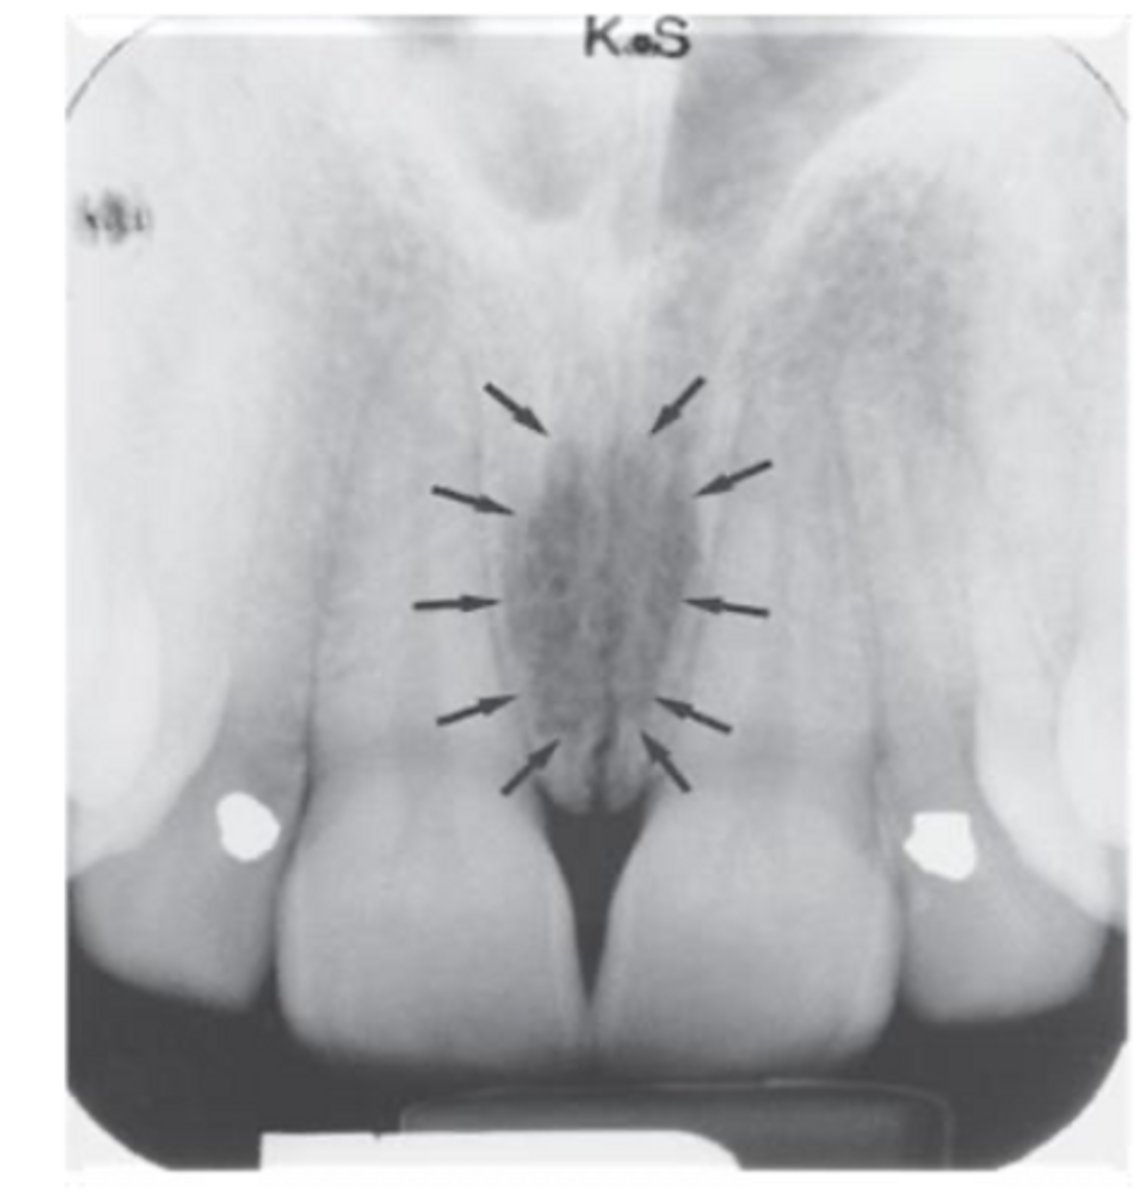

ID the structure:

intermaxillary suture

nasopalatine foramen